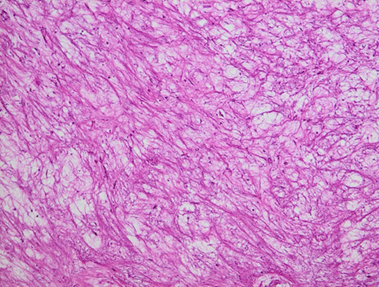

Histopathological analysis confirmed the diagnosis of Inflammatory sinonasal

polyp (Figure 5).

Figure 5. Histological section stained with hematoxylin and eosin (magnification

×20) the chorio is oedematous and the site of a polymorphic

inflammatory infiltrate composed of lymphocytes, plasma cells and neutrophils.